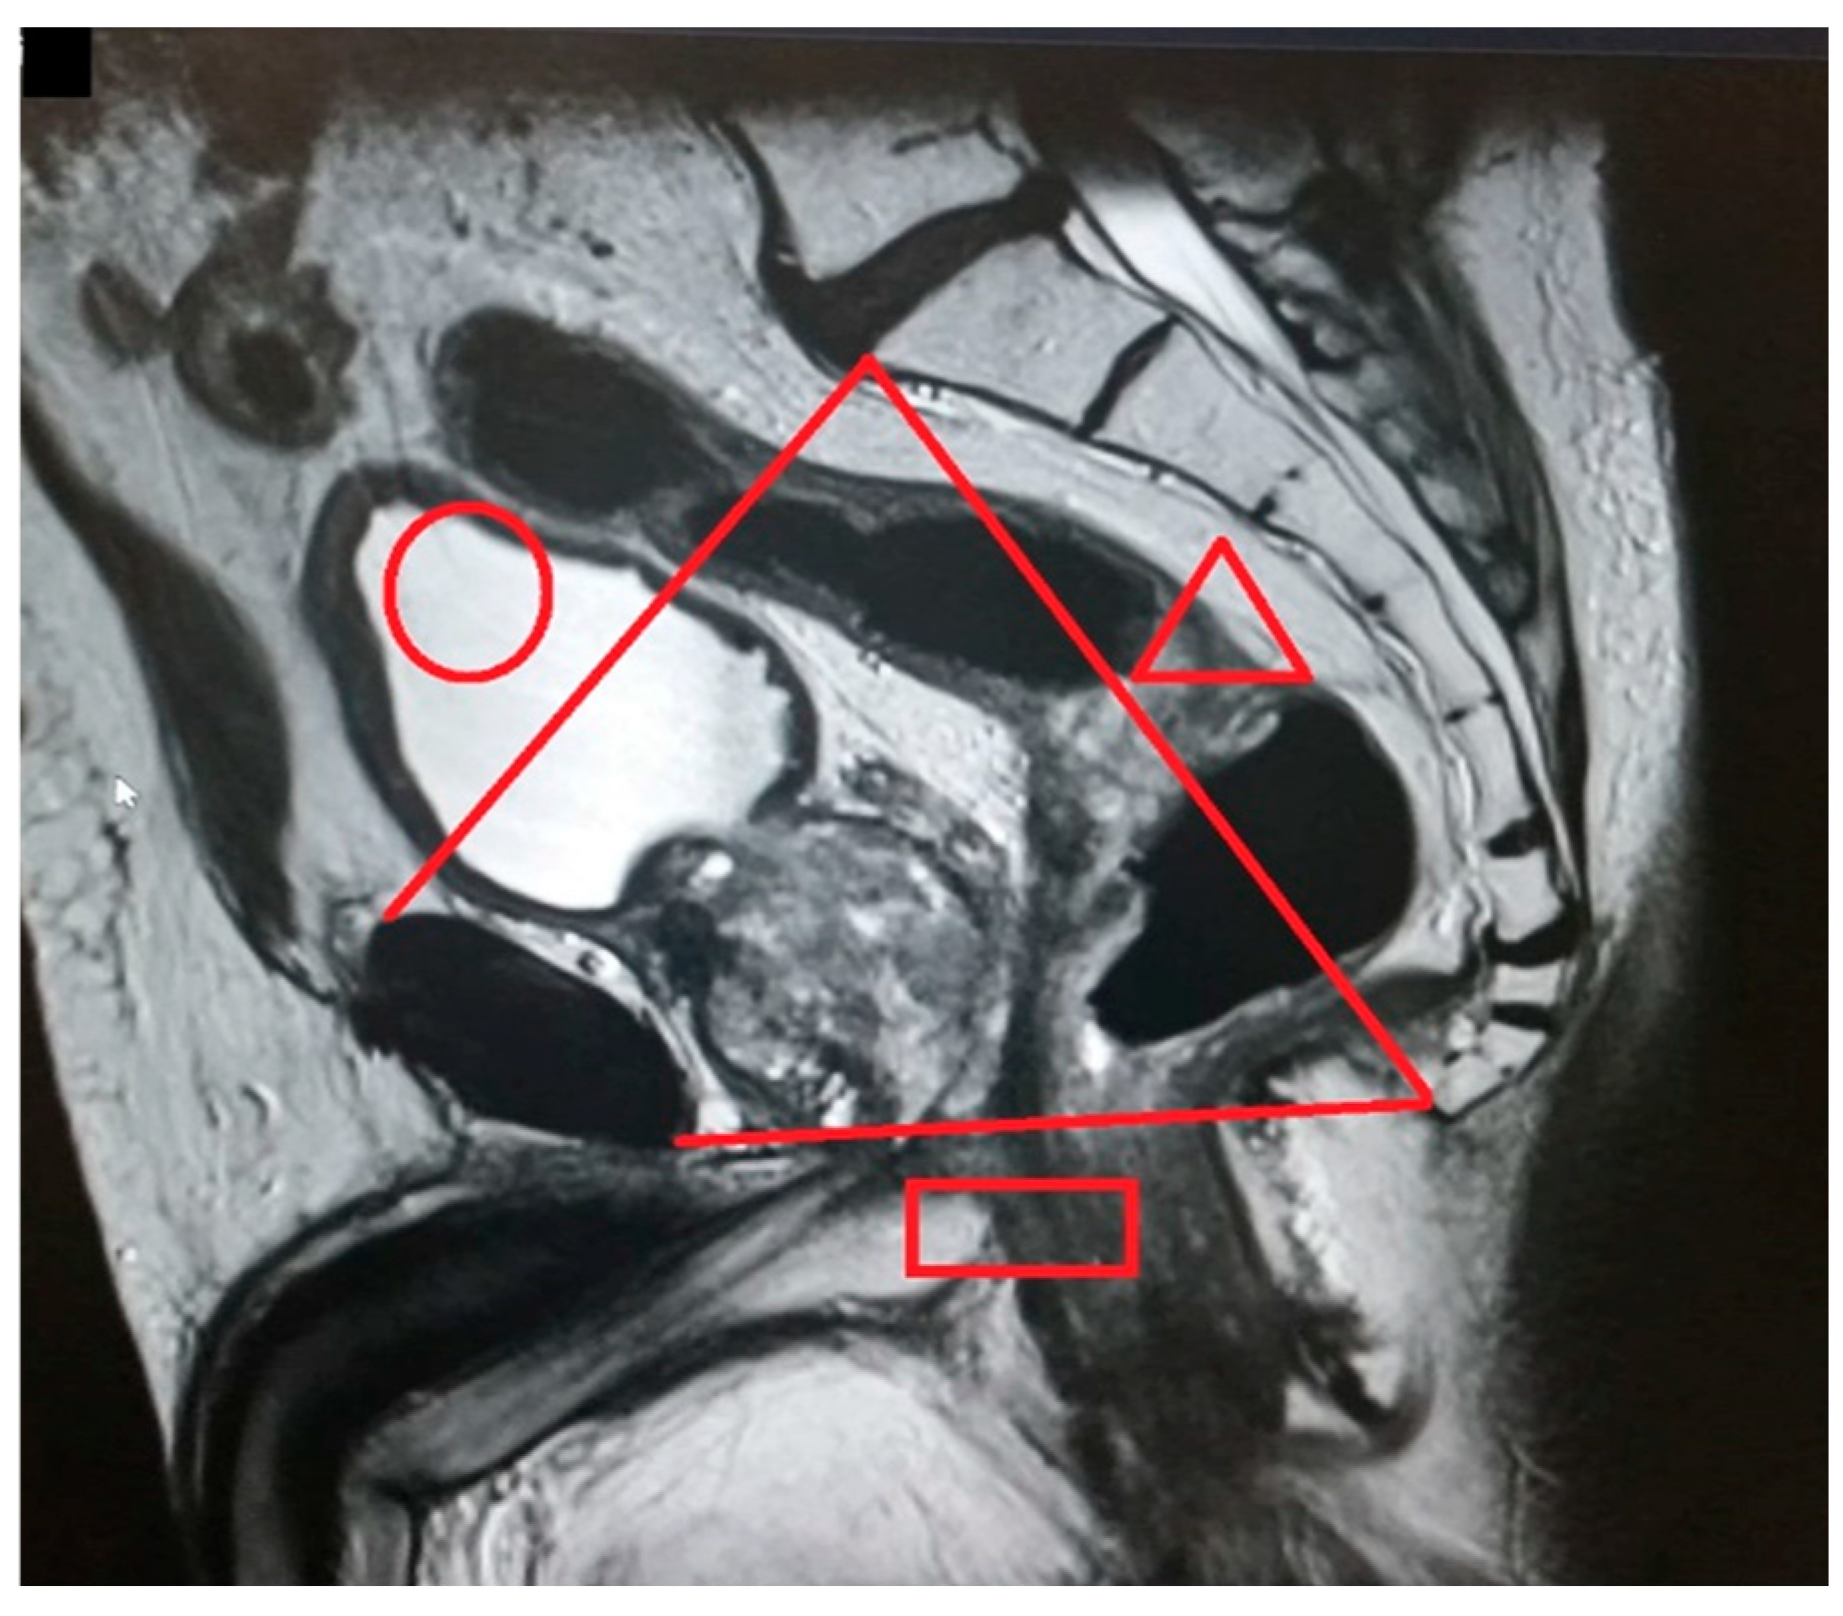

The pelvic measurements on MRI (Figure 2, Figure 3, Figure 4, Figure 5, Figure 6 and Figure 7) were carried out by the author, and to maintain the reproducibility of the results, measurements were taken, whenever possible, at the same anatomical levels.

Figure 2.

Pelvic inlet (circle): distance from the superior aspect of the pubic symphysis to the promontory). Pelvic outlet (rectangle): distance from the inferior aspect of the pubic symphysis to the tip of the coccyx). Pelvic depth (triangle): distance from the promontory to the tip of the coccyx.